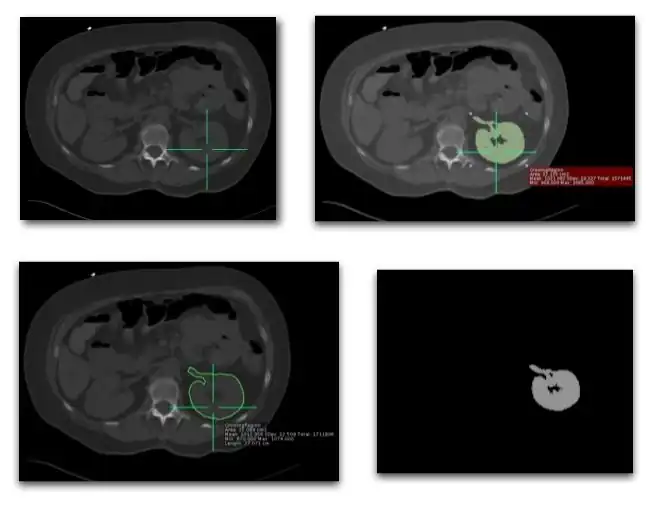

- Many forms of image analysis require the identification of structures and objects within an image. Image segmentation is the process of partitioning an image into distinct regions by grouping together pixels which belong to the same object. Two general approaches have been developed:

- Here some property of an image is compared to a fixed or variable threshold on a pixel-by-pixel basis. A simple example is a grey-level threshold where a look-up table (LUT) of the form illustrated in the left hand panel of Figure 5.13.5 is applied, and where the value of the threshold, T, can be adjusted interactively.

- This is a useful technique when the image contains a single, well-defined object or group of objects of similar pixel value superimposed on a background with a substantially different pixel value. However, difficulties can arise with grey-level thresholding when objects are close together, e.g. cardiac chambers. Histogram analysis can be used as an alternative where pixel values are thresholded on the basis of their frequency of occurrence, as illustrated in the right hand panel of the figure. Other alternatives include thresholding colours when a CLUT is applied, monitoring the time of arrival of a tracer or contrast medium in a region of an image and analysis of the variation in pixel values in the neighbourhood of a pixel within an object of interest.

- A common technique is based on firstly defining a starting pixel in the object and then testing neighbouring pixels on the basis of a specific criterion for addition to a growing region. This criterion could be based on pixel value considerations, as in Figure 5.13.6 for instance, or on the anticipated size or shape of the object.